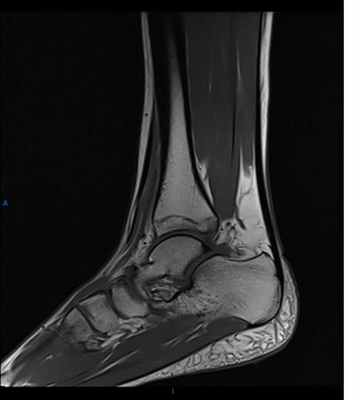

Диагностика повреждения голеностопного сустава устанавливается после травматологического обследования. Рентгенография голеностопа в прямой и боковой проекциях позволяет визуализировать переломы, но не указывает на повреждения суставно-связочного аппарата. МРТ голеностопного сустава при кисте таранной кости МРТ голеностопного сустава позволяет определить разрыв связок, воспаление, злокачественные новообразования мягких тканей, расположенный вокруг сустава. Цена магнитно-резонансной томографии в Москве около 6000 рублей, поэтому не каждый человек при отсутствии сильной боли, значительного ограничения подвижности голеностопного сустава захочет отдавать данную сумму денег. Только при появлении более серьезных проблем в последующем возникает желание, сделать МР-сканирование голеностопа. Цена при данной ситуации играет второстепенную роль. Предварительно нужно определиться с показаниями, а при необходимости не отказываться от МР-сканирования. Почему? Расскажем ниже. Ортопеды-травматологи отмечают значительное количество диагностических ошибок при использовании для диагностики лишь рентгенографии голеностопного сустава. При физикальном осмотре не всегда удается заподозрить повреждение суставно-связочного аппарата, особенно, если существенно не ограничена подвижность конечности. Практика показывает, что клиническая картина не отражает полноту всех изменений на раннем и позднем посттравматическом этапе. Использование для диагностики способа двухпроекционной планарной рентгенографии обладает низкой информативностью. Вследствие этого специалисты выставляют неполные или некачественные диагнозы. Большая вероятность диагностических ошибок при диагностике колеблется в пределах от 8 до 36%. Единственное показание для использования рентгенографии голеностопного сустава – подозрение на перелом костей. В статье будет описано, что показывает мрт голеностопного сустава. Многие современные врачи лучевой диагностики предлагают использовать обследование для верификации патологии мягкотканого компонента. Высокая информативность метода, специфичность – эти достоинства помогают своевременно установить диагноз, провести правильное лечение. Низкое качество диагностики патологии хрящевого и связочного компонента при рентгенографии голеностопного сустава не позволяет провести качественное своевременное определение патологии. Низкое качество диагностики требует поиска новых алгоритмов и способов диагностики. Скопление жидкости и рубцевания сухожилия на МРТ Внутрисуставные поражения хряща приводят к проблемам при ходьбе, поэтому рационально внедрение МРТ для определения патологии. Доступная цена исследования позволяет использовать магнитно-резонансную томографию для выявления хрящевых поражений. Нужно лишь разработать современные алгоритмы для использования МР-сканирования голеностопа. О них поговорим несколько ниже.

При подозрении на изолированные поражения голеностопа применяется рентгенография. Способ позволяет выявить нарушения соотношений между костными структурами сустава, определить состояние капсулы, хрящевых замыкательных пластин. Магнитно-резонансная томография голеностопа при разрыве дельтовидной связки После сканирования повышается вероятность своевременной диагностики переломов, верификации костных изменений. Для определения других повреждений требуется смена режима. Суставно-связочный аппарат на томограммах хорошо визуализируется при T2-взвешенном режиме. Поражение передней таранно-малоберцовой связки позволяет визуализировать отрыв костного фрагмента. Трехмерное моделирование позволяется визуализировать суставные структуры в пространственном отношении. Картина помогает хирургу более объективно представить характер последующих оперативных вмешательств. Практические обследования показали, что магнитно-резонансная томография – это неинвазивный, безопасный метод. Исследование позволяет верифицировать практически все патологические изменения суставно-капсульного аппарата при использовании современных алгоритмов: • Предоперационная магнитно-резонансная томография характеризуется высокой степенью вариабельностью. По данным исследованиям – специфичность и чувствительность находится в пределах от 30 до 100%. Такие разбежки определяются оборудованием, квалификацией специалистов. При чтении томограмм иногда существует недооценка степени повреждения передней крестообразной связки, хрящевых структур; • МРТ голеностопного сустава с контрастом позволяет верифицировать характер внутрисуставного поражения, определить целостность тканей, исследовать связки; • Низкопольная томография обладает высокой точностью при необходимости верифицировать повреждение хряща для последующей операции; • После операции назначение МРТ голеностопа рационально даже при наличии металлических пластин, фиксаторов. Максимальная степень вариабельности повреждения передней крестообразной связки на фронтальном срезе показывает на томограмме линейные участки ослабления сигнала; • Т2-взвешенное картирование при обследовании суставного хряща позволяет выявить начальные проявления артроза голеностопного сустава; • Несмотря на высокую цену магнитно-резонансной томографии, применение стандартных алгоритмов снижает затраты на исследование примерно на 30%. В практической травматологии в Москве более распространена рентгенография и компьютерная томография, но специалисты редко используют для диагностики МР-сканирование, поэтому вероятность диагностических ошибок сохраняется на высоком уровне. Стоимость МРТ голеностопа не так высоко, чтобы игнорировать возможное повреждение тканей. Практическая ценность магнитно-резонансной томографии при артроскопии достаточно высока. По европейским стандартам для диагностики состояния пациента перед оперативным вмешательством обязательно проведение МР-сканирования. Артроскопия – это зондовое обследование внутренней суставной полости. Перед манипуляцией необходимо изучение суставных поверхностей, так как во время оперативного вмешательства возможно удаление лишних тканей, прижигание, отсасывание воспалительной жидкости. Для улучшения качества магнитно-резонансной томографии требуется использование высокопольных томографов. Согласно стандартной методике для обследования суставов требуется выполнение трехплоскостного сканирования. Для повышения качества диагностики требуется подавление сигнала от жировой ткани. Для оценки передней крестообразной связки делают наклонные томограммы. Трехмерные программы лучше использовать для анализа структуры передней крестообразной связки. Одновременно существует возможность для обследования хряща, связок. Использование МРТ-артрографии голеностопного сустава невозможно при наличии металлических имплантов. В такой ситуации рекомендуется КТ-артрография. При сочетании магнитно-резонансной томографии с рентгенографией удается оценить расположение металлических фиксаторов, поэтому такая диагностика рекомендована в послеоперационном периоде. МР-артрография используется для верификации внутрисуставной патологии при наличии клинических признаков послеоперационных изменений.

На рентгенограмме в переднее-задней проекции основными проявлениями недостаточности синдесмоза являются расширение вилки голеностопного сустава, расширение медиальной суставной щели и наклон таранной кости во фронтальной плоскости, травматическая эрозия плафона большеберцовой кости. Задний вывих малоберцовой кости в дистальной части голени виден, как заднее смещение малоберцовой кости относительно большеберцовой кости. Делают рентгенограммы с внутренней и наружной ротацией голени на которых имеется асимметрия суставной щели, расширение вилки голеностопного сустава, смещение наружной лодыжки назад и наклон таранной кости. Синдесмоз может оказаться поврежденным при отсутствии рентгенологических изменений. Самым информативным методом, который позволяет рассмотреть состояние отдельных связок, выявить дефект синдесмоза и определить соотношение костей голени является МРТ.